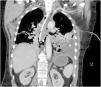

Mujer de 67 años que ingresa en la UCI en shock distributivo refractario. La radiografía de tórax (fig. 1) evidencia hidroneumotórax izquierdo, con separación de hojas pleurales apical de 5cm y desplazamiento mediastínico contralateral (

). La TC (fig. 2) confirma hidroneumotórax, y evidencia empiema pleural y neumomediastino periesofágico en tercio inferior esofágico (). Se realiza drenaje torácico, saliendo aire y líquido de aspecto turbio maloliente, con «abundantes bacterias, gotas de grasa y fibras sugerentes de restos alimenticios». Ante la sospecha de perforación esofágica, se realiza nueva TC con contraste oral (fig. 3) demostrándose extravasación de contraste a nivel del margen lateral izquierdo del esófago inferior, en relación con perforación, y paso de contraste a la cavidad pleural izquierda (). Se realiza cirugía urgente.Contribuciones de autoríaTodos los autores han realizado conjuntamente y a partes iguales la revisión, selección y redacción del artículo.